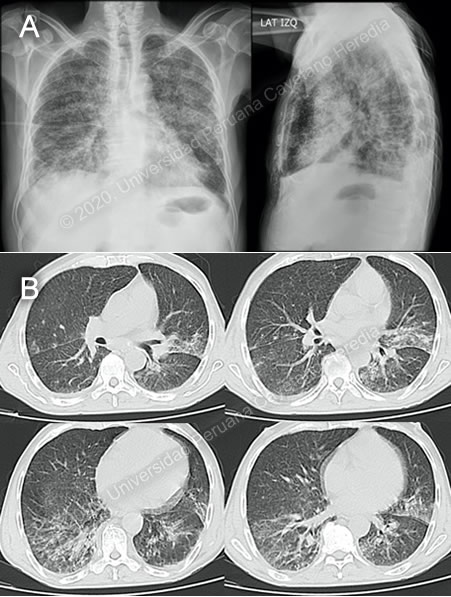

History: A 60-year-old male patient presented to the hospital complaining of 10 weeks of fever, night sweats and weight loss. 8 weeks before admission, he presented to a local physician with mild diffuse abdominal pain, and watery diarrhea, and is treated with ciprofloxacin for 7 days, with remission of the diarrhea. Over the next 2 weeks, he develops anorexia and asthenia, accompanied by worsening abdominal pain. He is treated with ivermectin, but his symptoms show no improvement. A month prior to admission, he starts noticing dyspnea, which steadily progresses and by the day of admission to the Tropical Medicine ward is present at rest. Epidemiology: Born and lives in Moyobamba, San Martin (tropical jungle of Peru). Worked as a farmer until 2005 but is currently unemployed. Raises chickens around his house and also has dogs. Past medical history includes cryptococcal meningitis in 2008. The patient denies other past illnesses and surgeries. No known TB contacts. Physical Examination: BP: 90/70 mmHg; RR: 24; HR: 116; T: 38°C. Presented with marked pallor; no rash or petechiae. No mucosal lesions. Palpable bilateral inguinal lymphadenopathy, about 3cm in diameter. Pulmonary exam revealed bilateral diffuse crackles. Cardiovascular exam was unremarkable. Abdomen was not distended but slightly tender to palpation, liver span ±15cm, no splenomegaly. Patient was alert, oriented, with no focal deficits, and no meningeal signs. Imaging Studies: CXR revealed bilateral interstitial infiltrates (Image A). Thoracic CT showed interstitial infiltrates in both inferior lobes and the left superior lobe, with bilateral bronchiectasis and mediastinal lymphadenopathy(Image B). Abdominal CT revealed discrete hepatomegaly. Laboratory: Hb 8.9 g/dL; Hct 28%; WBC 4.64 (bands 0%, neutrophils 71.1%, eosinophils 1.3%, basophils 0.2%, monocytes 9.3%, lymphocytes 16.8%); Platelets 163 000. Gluc 103 mg/dL, Urea 37 mg/dL, Creat 0.7 mg/dL, Na 133 mEq/L, K 3.57 mEq/L, Cl 99 mEq/L, Total bilirubin 0.3 mg/dL, Indirect bilirubin 0.2 mg/dL, Alk phos 169, AST 108, ALT 50, GGT 107, LDH 291 (N=???), CRP 197.7, HIV and HTLV non-reactive. Blood cultures x2: negative. AFB, GeneXpert MTB/RIF, culture in BAL for bacteria and mycobacteria: negative. |